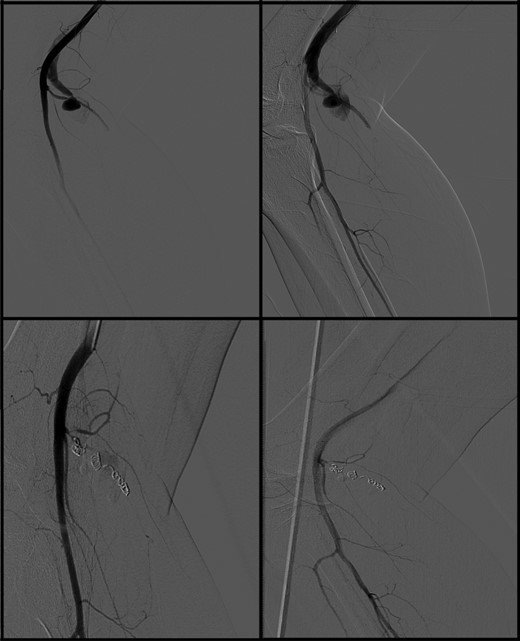

Immediately postoperatively the patient reported progressive pain in the popliteal fossa. The patient was discharged the same day with adequate pain medicine (paracetamol, celecoxib and tramadol). Eight days postoperative, the patient was sent in by his GP with the same complaints and a substantial hematoma in his popliteal space. Sensibility and pulsations were intact. A lower extremity ultrasound showed an active bleeding (28 × 19 mm) of the sural artery with a thrombosed hematoma of 71 × 41 mm. Within 2 h, a digital subtraction angiography via the ipsilateral common femoral artery (CFA) was performed and showed an active blush and an arteriovenous (AV) fistula with proximal filling out of two branches (Fig. 1). The lesion was coiled (Tornado® Embolization Coil, Cook Medical, Bloomington, USA) both proximal and distal. The puncture in the CFA was closed with an angio-seal (St Jude Medical, Inc., St Paul, USA). After this intervention, the pain reduced and discharge followed after 2 days.

Digital subtraction angiography showed active blush of the sural artery and AV fistula with proximal filling (upper two images). After coiling procedure, hemostasis was accomplished (lower two images).